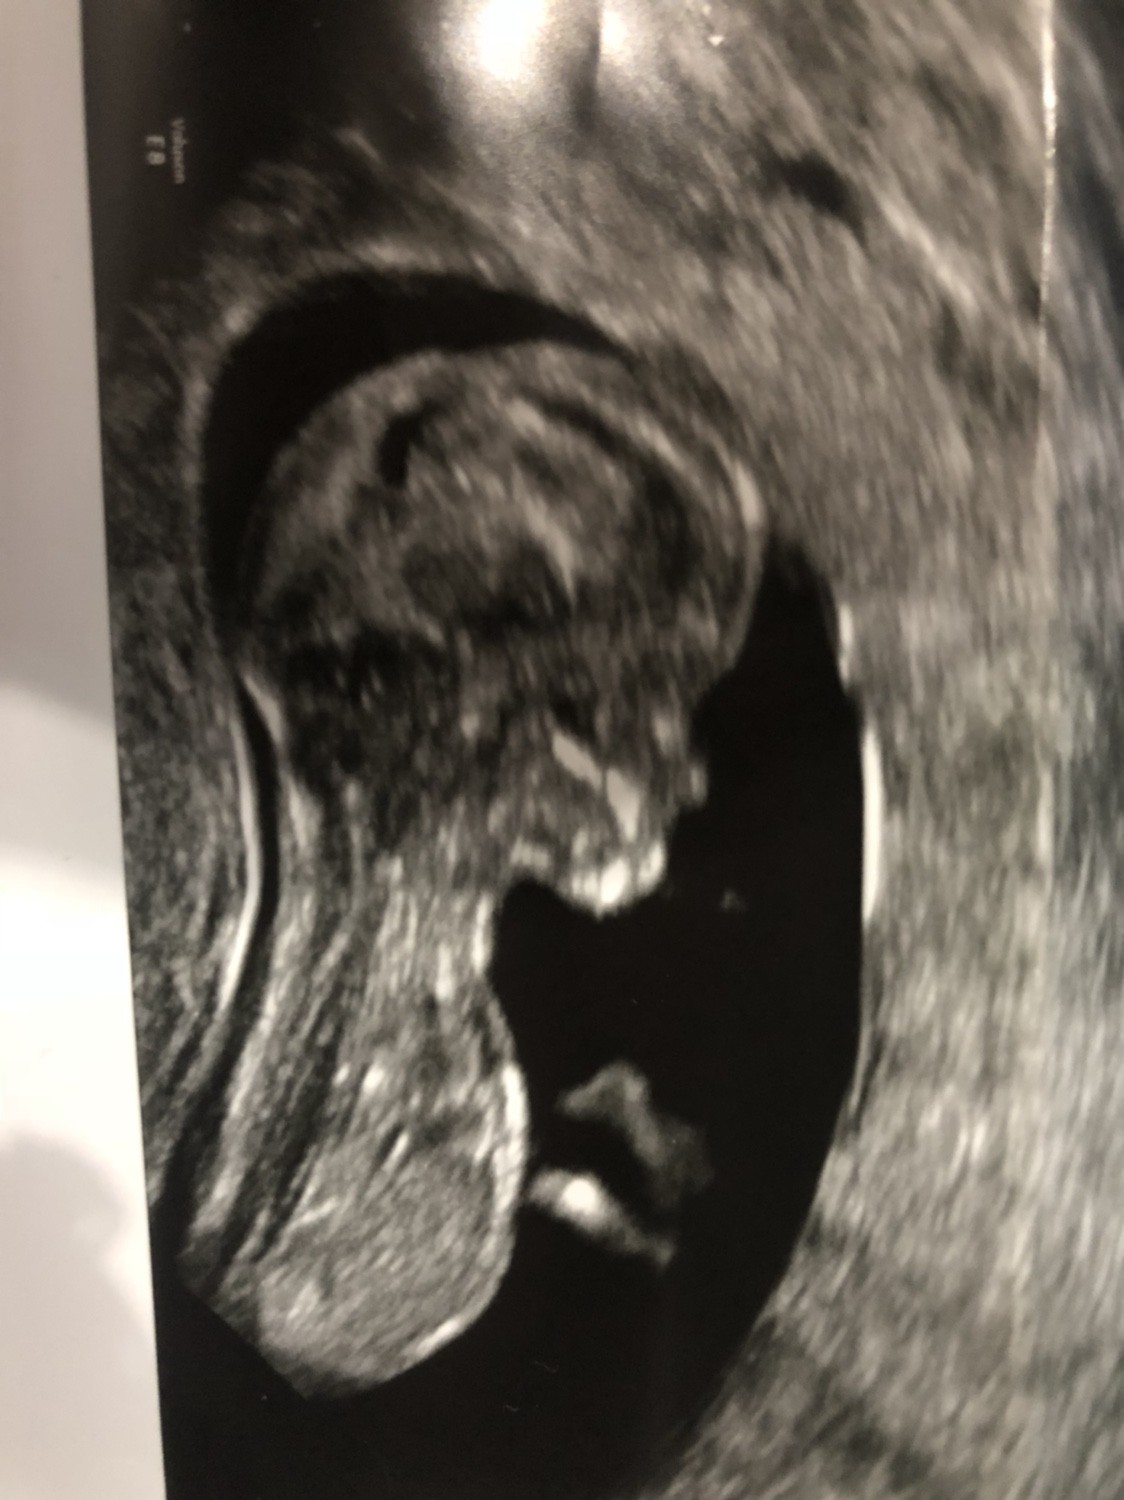

Dziewczyny, jestem już po wizycie. Nie byłam w stanie napisać wcześniej, bo tak schodził ze mnie ten stres,że aż się popłakałam. Wszystko jest dobrze [emoji173]️ kamień z serca. Lekarz powiedział,że prawdopodobnie to dziewczynka,ale żeby się nie nastawiać ( za późno [emoji23]). Cieszę się,że zdecydowałam się iść wcześniej,prywatnie,bo teraz mam spokojna głowę.

Bardzo Wam dziękuje za wsparcie [emoji173]️ nie pomyślałabym nigdy,że na takim forum można poznać takie cudowne kobiety, które tak pięknie wspierają się nawzajem. Jeszcze raz dziękuje kochane [emoji173]️

IMG_5936.JPG

I jakie śliczne zdjęcie ;)